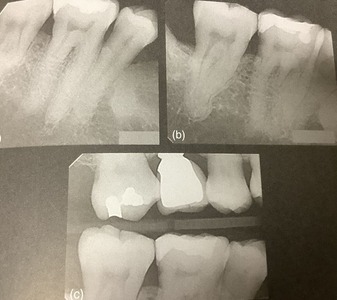

削り始める前に

神経の形、特徴を良く見極めるために、

レントゲンを良く良く観ます。

神経の本数、形の特徴、曲がり具合、細くなっていないか?などです。

分かっていれば、適した器具を選べ、どのステップが難しそうかを予想して準備ができます。

この歯、下の6番、第一大臼歯には

手前の根っ子は1本でその中に2本の神経が、後側には2本の根っ子が分かれているようです。

後のベロ側にある根っ子はアジア人に多くて、ラディックス エントモラーリスって言いますが、日本語では?

人種差があって、0.9〜22.4%に見られます。

他よりも薄くて短いのが多く、頬側に強烈に曲がっています。

入り口はベロ側、やや手前よりのあります。

難しい根管です。

この歯はチョット根が長いです。

根っ子の先3分の1辺りが少し曲がっています。